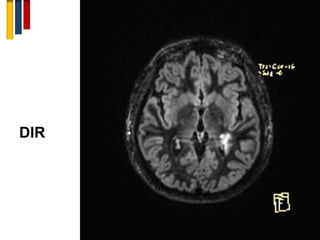

5. Double inversion recovery (DIR)

A sequence that suppresses both CSF and white matter signal

for better delineation of the plaques.

DIR